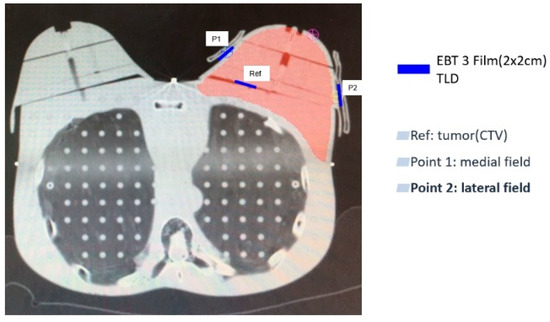

| Median Dose | P1 (Medial Field) | P2 (Lateral Field) | P1 (Medial Field) | P2 (Lateral Field) | P1 (Medial Field) | P2 (Lateral Field) | ||||||||||||||||||

| (cGy) | TPS | EBT3 Film | TLD | p Value | TPS | EBT3 Film | TLD | p Value | TPS | EBT3 Film | TLD | p Value | TPS | EBT3 Film | TLD | p Value | TPS | EBT3 Film | TLD | p Value | TPS | EBT3 Film | TLD | p Value |

| (IQR) | ||||||||||||||||||||||||

| Without PERSBRA | 25.88 | 100.34 | 89.92 | 0.25 | 41.44 | 132.83 | 112.90 | 0.25 | 25.21 | 106.49 | 88.29 | 0.25 | 40.56 | 147.20 | 119.87 | 0.25 | 44.93 | 130.36 | 100.40 | 0.25 | 64.25 | 149.26 | 99.86 | 0.25 |

| (2.65) | (3.70) | (1.74) | (3.50) | (5.54) | (1.11) | (1.02) | (5.14) | (1.16) | (4.57) | (3.44) | (6.10) | |||||||||||||

| Large Mesh PERSBRA | 92.18 | 172.08 | 157.73 | 0.25 | 136.55 | 172.80 | 171.05 | 0.25 | 89.36 | 163.98 | 169.94 | 0.50 | 131.98 | 170.58 | 165.28 | 0.5 | 91.51 | 160.96 | 148.47 | 0.25 | 96.60 | 159.95 | 156.16 | 0.5 |

| (5.03) | (11.12) | (2.79) | (3.28) | (1.59) | (8.00) | (1.48) | (4.96) | (0.67) | (3.55) | (5.20) | (2.06) | |||||||||||||

| Fine Mesh PERSBRA | 133.56 | 184.06 | 179.29 | 0.75 | 160.57 | 194.12 | 196.76 | 1 | 151.84 | 180.50 | 183.12 | 0.25 | 153.13 | 202.50 | 201.66 | 0.25 | 157.18 | 166.08 | 156.07 | 0.5 | 132.74 | 202.42 | 194.65 | 0.25 |

| (7.67) | (13.24) | (5.28) | (3.98) | (2.38) | (1.55) | (0.90) | (3.90) | (2.77) | (7.13) | (0.75) | (6.47) | |||||||||||||

| Solid PERSBRA | 157.04 | 184.52 | 182.15 | 1 | 160.24 | 195.34 | 199.78 | 0.25 | 158.77 | 181.07 | 184.51 | 0.25 | 159.06 | 203.06 | 199.55 | 1 | 187.00 | 178.90 | 182.90 | 1 | 141.18 | 198.03 | 199.27 | 1 |

| (1.81) | (4.88) | (0.93) | (1.07) | (0.44) | (4.33) | (0.56) | (6.01) | (4.19) | (15.67) | (2.76) | (3.01) | |||||||||||||